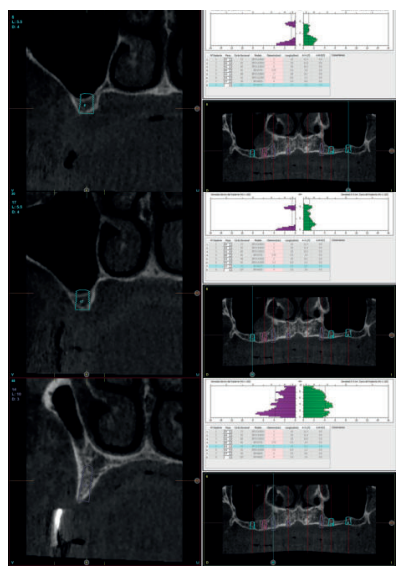

Se realiza un CBCT dental para la planificación del caso y poder rehabilitar el maxilar superior e inferior. En la mandíbula se planifica retirar los dos implantes de forma atraumática (mediante el kit de extracción a contra-torque) y la inserción de cuatro implantes para la confección de una nueva prótesis implanto-soportada. Los cortes de planificación muestran la necesidad de que los implantes insertados sean cortos y algunos de ellos, como el caso del implante en posición 44, por lingual del nervio dentario. (Figuras 5-7).

En el caso del maxilar superior, la atrofia es combinada, existiendo una gran atrofia vertical en los sectores posteriores que requiere la inserción de implantes cortos y extra-cortos, para evitar una elevación de seno a ese nivel. En las zonas anteriores (de premolar a premolar) existe una extrema reabsorción horizontal que obliga a la inserción de implantes estrechos, siendo los seleccionados cuatro implantes de plataforma reducida (3.0) y un implante de plataforma reducida Core en una zona de transición entre la atrofia anterior y posterior, que presenta una atrofia mixta (zona de 15-16) (Figuras 8-10).